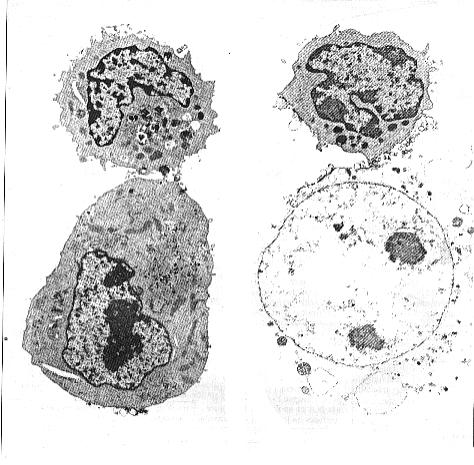

Etude de documents Lymphocytes T8 et Lymphocytes cytotoxiques: la reconnaissance de l'AG présenté par une cellule infectée (ou cancéreuse...) => une immunité à médiation cellulaire

III Les étapes de la réponse immunitaire adaptative à médiation cellulaire